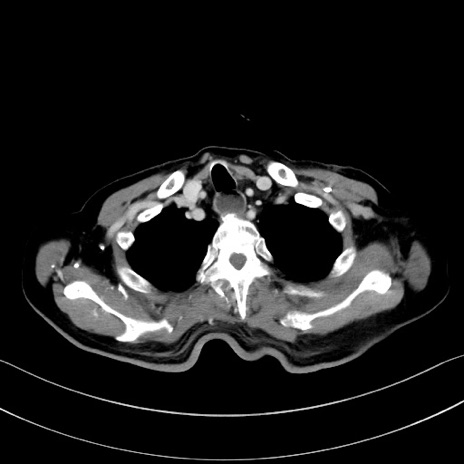

冠状断像

【症例】60歳代男性

【主訴】嘔吐

【現病歴】胃癌にて胃全摘後。食思不振が悪化し、夜中に嘔吐することがある。

【既往歴】胃癌、胃全摘、脾摘、胆摘後

【データ】WBC 5900、CRP 10.56